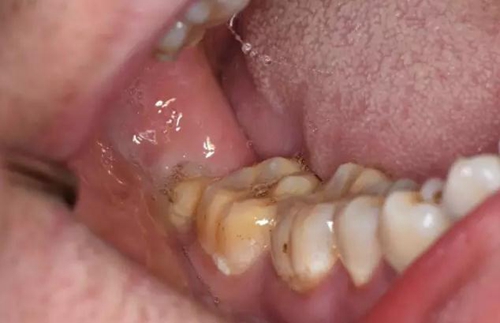

患者、胡xx、男、23歲。主訴:右側(cè)面頰部反復腫痛一月余。口腔??茩z查:右側(cè)前頰部有約1.5cmx2.0cm大小的腫脹。捫診有波動感、觸診疼痛,開口度正常。??茩z查:48垂直位。遠中有深的盲袋。全景片顯示:48融合根。頜骨未見異常。診斷:48冠周炎繼發(fā)皮瘺。治療計劃:建議拔除48并口外切開引流?;颊咄庵委煼桨福炐g前知情同意書。

圖3.口內(nèi)檢查:48垂直阻生、有盲袋、牙冠萌出3/4,36、37牙齒健康。